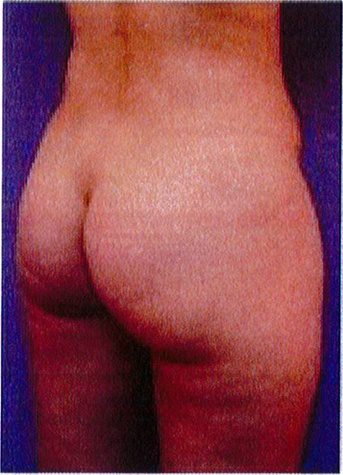

Hình. 20. (A) Hình anh trước và (B) và sau phẫu thuật làm đầy mông của bệnh nhân có vùng mông tương đối đầy đặn. Bệnh nhân được đặt khối implant dưới cân thể tích 330 mL ở hai bên.

THỜI GIAN HỒI PHỤC SAU MỔ

Bệnh nhân 30 tuổi mong muốn cải thiện hình dáng vòng ba, mặc dù vòng mông đã tương đối đây đặn. Bác sĩ sau khi đánh giá đã đưa ra quyết định hút mỡ eo và làm đầy mông bằng implant. Hai khối implant microtextured (vi nhám) thể tích 330 mL được đặt cân đối ở hai bên. Bệnh nhân sau phẫu thuật xuất hiện bục một phần vết mổ (dài khoảng 2cm) ở hai bên nhưng không sâu và đã điều trị kịp thời bằng dung dịch sát khuẩn, kháng sinh tại chỗ và toàn thân. Vết mổ liền lại tốt (Hình 20).